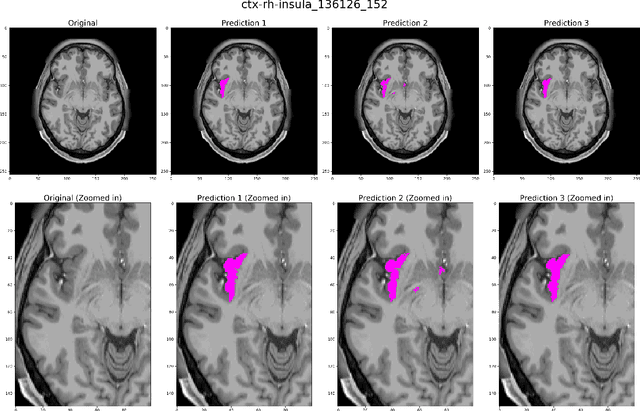

Abstract:Quantitative, volumetric analysis of Magnetic Resonance Imaging (MRI) is a fundamental way researchers study the brain in a host of neurological conditions including normal maturation and aging. Despite the availability of open-source brain segmentation software, widespread clinical adoption of volumetric analysis has been hindered due to processing times and reliance on manual corrections. Here, we extend the use of deep learning models from proof-of-concept, as previously reported, to present a comprehensive segmentation of cortical and deep gray matter brain structures matching the standard regions of aseg+aparc included in the commonly used open-source tool, Freesurfer. The work presented here provides a real-life, rapid deep learning-based brain segmentation tool to enable clinical translation as well as research application of quantitative brain segmentation. The advantages of the presented tool include short (~1 minute) processing time and improved segmentation quality. This is the first study to perform quick and accurate segmentation of 102 brain regions based on the surface-based protocol (DMK protocol), widely used by experts in the field. This is also the first work to include an expert reader study to assess the quality of the segmentation obtained using a deep-learning-based model. We show the superior performance of our deep-learning-based models over the traditional segmentation tool, Freesurfer. We refer to the proposed deep learning-based tool as DARTS (DenseUnet-based Automatic Rapid Tool for brain Segmentation). Our tool and trained models are available at https://github.com/NYUMedML/DARTS